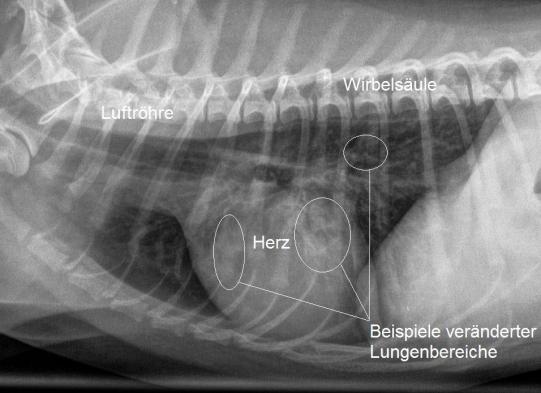

Aus diesem Grund werden nun Lungenröntgen angefertigt. Auf den Bildern sind leichte bis mittelgradige, diffus verteilte Lungenverschattungen vom sogenannt bronchointerstitiellen Typ erkennbar. Als mögliche Ursachen kommen bei diesem Typ Lungenveränderung neben einer chronischen bakteriellen Bronchitis insbesondere ein Infekt mit Lungenwürmern in Frage. Da ein Breitspektrumantibiotikum keine Verbesserung des Hustens bewirkt hatte, scheint ein Lungenwurmbefall nun sehr wahrscheinlich.